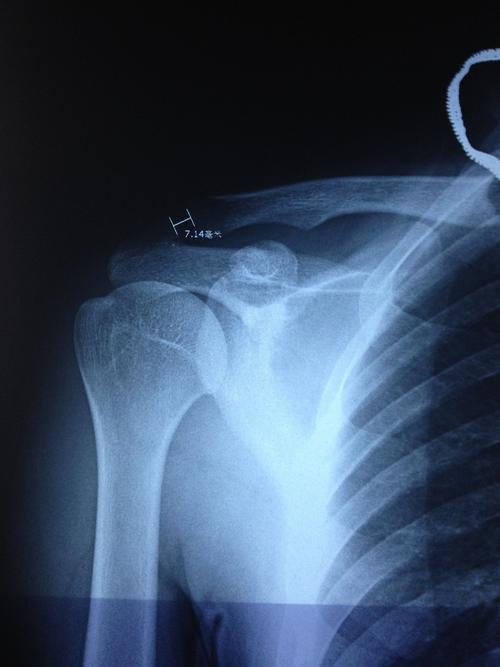

肩锁关节脱位三度图片

肩锁关节脱位三度图片,肩锁关节脱位二度图片

肩锁关节脱位

肩锁关节脱位二度图片

肩锁关节脱位图片

肩锁关节脱位三度分型

三度肩锁骨脱位图片

肩锁关节脱位三度

肩锁关节脱位x线图片

肩锁关节半脱位图片